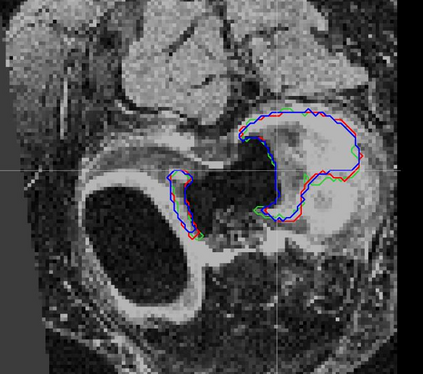

Direct automatic segmentation of objects from 3D medical imaging, such as magnetic resonance (MR) imaging, is challenging as it often involves accurately identifying a number of individual objects with complex geometries within a large volume under investigation. To address these challenges, most deep learning approaches typically enhance their learning capability by substantially increasing the complexity or the number of trainable parameters within their models. Consequently, these models generally require long inference time on standard workstations operating clinical MR systems and are restricted to high-performance computing hardware due to their large memory requirement. Further, to fit 3D dataset through these large models using limited computer memory, trade-off techniques such as patch-wise training are often used which sacrifice the fine-scale geometric information from input images which could be clinically significant for diagnostic purposes. To address these challenges, we present a compact convolutional neural network with a shallow memory footprint to efficiently reduce the number of model parameters required for state-of-art performance. This is critical for practical employment as most clinical environments only have low-end hardware with limited computing power and memory. The proposed network can maintain data integrity by directly processing large full-size 3D input volumes with no patches required and significantly reduces the computational time required for both training and inference. We also propose a novel loss function with extra shape constraint to improve the accuracy for imbalanced classes in 3D MR images.